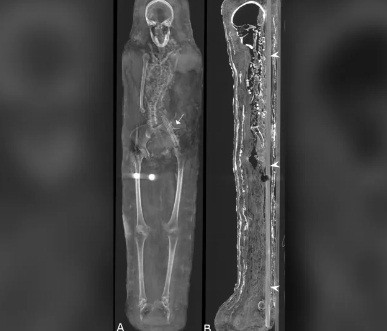

Kết quả kiểm tra cho thấy 2 xác ướp này qua đời vào khoảng năm 30 trước Công nguyên đến năm 395 sau Công nguyên.

Hai người này qua đời khi còn khá trẻ. Trong khi người đàn ông cao 1,64m qua đời khi khoảng 25 - 30 tuổi thì người phụ nữ có chiều cao 1,56m chết khi 30 - 40 tuổi.

Bên cạnh 2 xác ướp, giới nghiên cứu còn tìm thấy một số cổ vật khác như vòng cổ và tiền xu. Trong số này, tiền xu được cho là để người chết dùng trả cho thần Charon. Vị thần này chuyên chèo thuyền đưa linh hồn của người quá cố qua sông Styx đến thế giới bên kia.